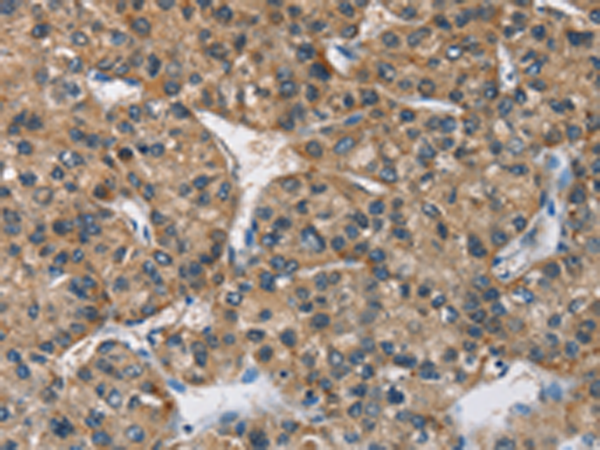

分类: 科研抗体货号: P07122别名: HB16; CREB2; TREB7; CRE-BP1应用: IHC反应种属: Human, Mouse, Rat